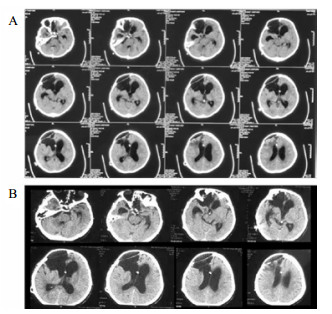

病例3,患者男,76岁,因“突发头痛昏迷,动脉瘤栓塞脑室引流术后半年余,脑积水分流术后3个月”入院。入院体查:GCS 7分,植物状态,双巴氏征阳性。V-P分流调压阀压力为1.0,脑积水虽已行分流术,但脑室仍明显扩大。拟诊:左前交通动脉瘤栓塞术后,脑积水V-P分流术后,持续性植物状态。脑室压力低于外耳道连线5 cm, 持续外引流脑脊液100~200 mL/d,同时去枕卧位,腹带加压包扎,适当增加补液量和扩脑血管改善脑微循环,力求增加颅内压和脑顺应性。脑室压力逐渐上升,然后调压至0.5,期间多次复查未见脑室大小明显缩小;但患者出现对威胁有眨眼反应,偶尔能对视觉对象定位,转为微小意识状态。发病4年后,即80周岁时,因为肺部感染而再次入院,控制肺部感染期间,考虑脑室仍扩大状态,予按压分流阀600次/d,患者意识显著上升,能主动要求饮食并表达喜好,能和家属互动做简单游戏。随访头颅CT见脑室较前有所缩小(图 5C)。

| A:第一次入院CT(脑出血栓塞和脑室外引流后);B:常规治疗后脑室扩大仍明显;C:2018年7月5日随访 图 5 病例3 CT |

病例4,男,26岁,因“车祸致颅脑损伤昏迷6个月”而入我院。急诊行开颅血肿清除术后1个月因脑积水而行V-P分流术。入院体检:GCS 7分,植物状态,四肢肌张力高,双巴氏征阳性。入院诊断为:重型颅脑损伤术后,脑积水V-P分流术后,持续性植物状态(图 6A)。考虑V-P分流过度引流,将分流调压阀调至最高的2.5水平,骨窗压力和头颅CT没有明显改变。遂将分流管皮下缝扎完全阻断,骨窗压力逐渐升高,术后复查CT(图 6B), 同时患者意识水平改善至微小意识状态。因脑积水加重再行V-P分流术,并择期予右额颞颅骨修补重建,随访头颅CT见图 6C。随后患者恢复至GCS 15分。

| A:男,26岁,颅脑损伤术后6个月入院时头颅CT;B:2015年1月4日分流管缝扎后CT;C:2017年3月8日V-P分流和颅骨修补术后 图 6 病例4 CT |